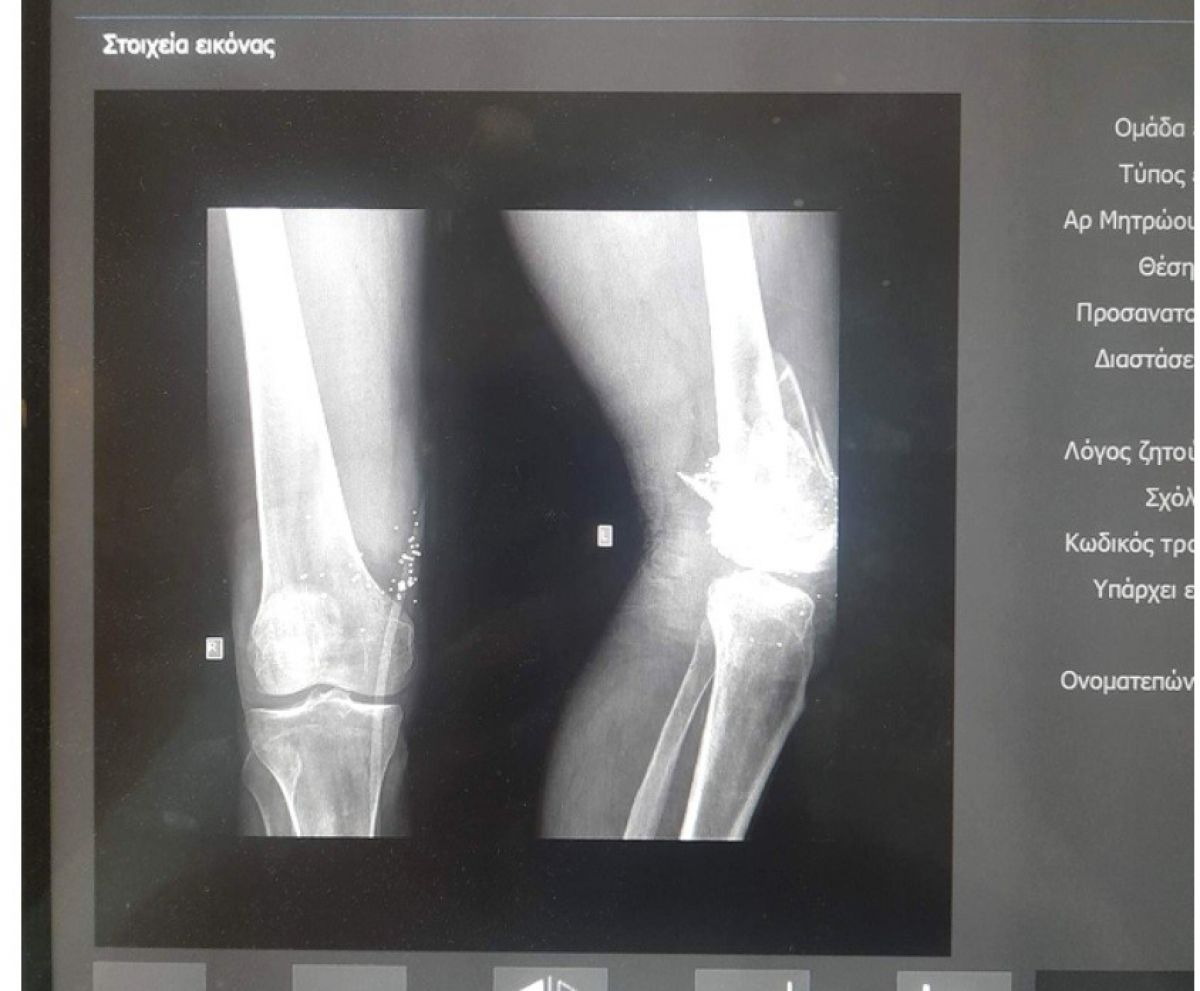

Victima riscă să i se amputeze un picior

Din cauza faptului că nu vorbește engleză, unchiul său nu a știut până recent care este cu adevărat situația sa medicală. Mai mult decât atât, chiar dacă la un picior are fractură, iar la celălalt este rănit, și-a asigurat familia că nu trebuie să își facă griji, el bazându-se pe ajutorul preotului, care însă nu l-a mai căutat. Când a aflat că a fost abandonat în spital de cel care l-ar fi împușcat și care i-ar fi promis sprijin, familia bărbatului a plecat de urgență în Grecia.

”Pur și simplu, timp de o săptămână, a fost al nimănui. Ieri am reușit să îi recuperăm buletinul, cu ajutorul Poliției. Unchiul este în stare critică, urmează să facă niște operații și riscă să i se amputeze un picior. A fost lăsat ca un câine acolo. El spera, săracul, că mai stă pe aici, prin Grecia, dar nu o să mai meargă normal niciodată. Dacă nu veneam aici, tare mi-e că îl luam acasă între patru scânduri”,